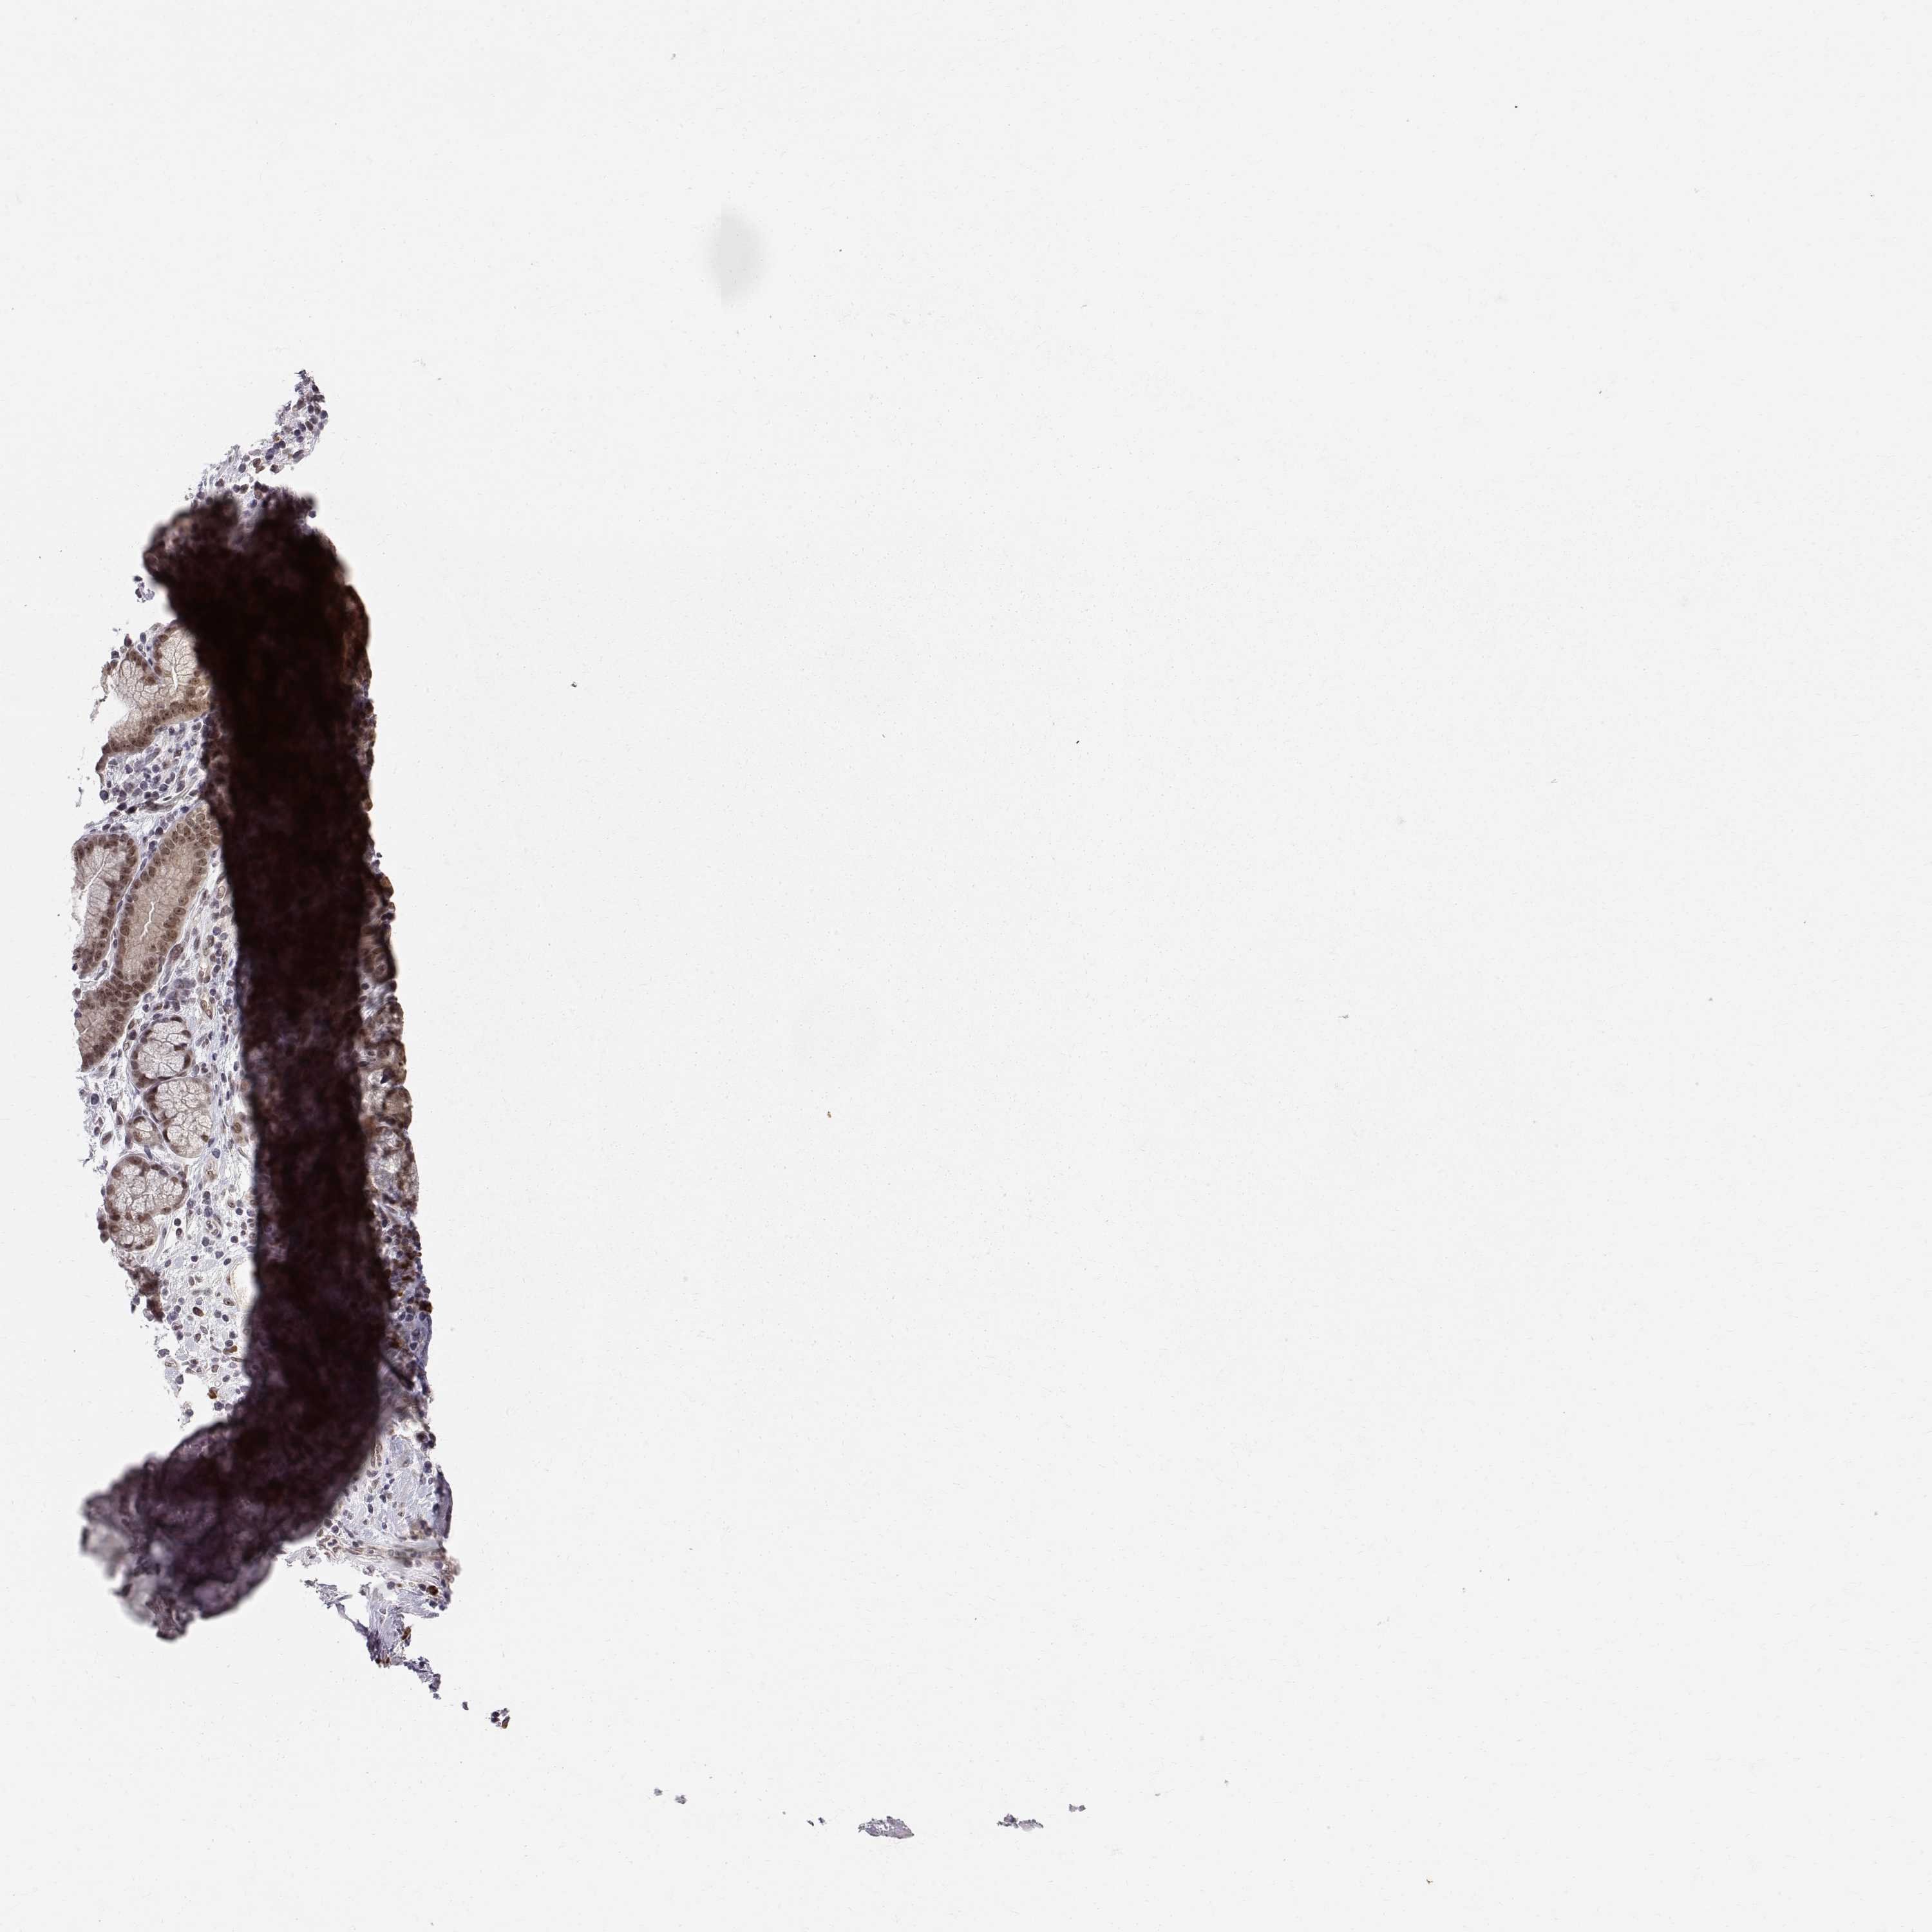

STOMACH CANCER - Protein expressioni

A mouse-over function shows sample information and annotation data. Click on an image to view it in a full screen mode. Samples can be filtered based on level of antibody staining by selecting one or several of the following categories: high, medium, low and not detected. The assay and annotation is described here.

Note that samples used for immunohistochemistry by the Human Protein Atlas do not correspond to samples in the TCGA dataset.

Antibody stainingi

Antibody staining in the annotated cell types in the current human tissue is reported as not detected, low, medium, or high, based on conventional immunohistochemistry profiling in selected tissues. This score is based on the combination of the staining intensity and fraction of stained cells.

Each image is clickable and will lead to virtual microscopy that enables deeper exploration of all samples and also displays staining intensity scores, fraction scores and subcellular localization as well as patient and tissue information for each sample.

Antibody HPA050398

Staining

High

Medium

Low

Not detected

Intensity

Strong

Moderate

Weak

Negative

Quantity

>75%

75%-25%

<25%

None

Location

Nuclear

Cytoplasmic/membranous

Cytoplasmic/membranous,nuclear

Adenocarcinoma, NOS

Adenocarcinoma, High grade